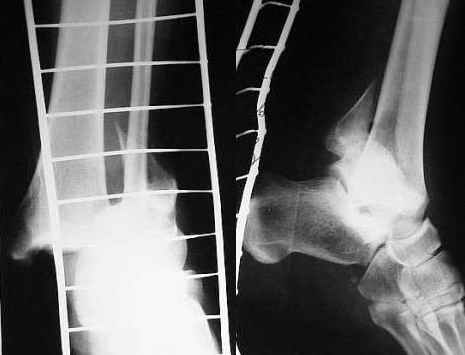

Стабильность г\ст сустава обеспечивается во-первых наружной лодыжкой (ключ), во-вторых задним краем б\б кости, в-третьих связками синдесмоза и межкостной мемраной, только в-четвертых медиальной лодыжкой (дельтовидной связкой. Это классика! А пяточной кости и плюсневых костей здесь нет! зачем их фиксировать? см. вложенный файл.

В подобных ситуациях пользовались упрощенной компоновкой аппарата. Спиц достаточно трех, все во фронтальной плоскости, с напайками: снаружи - в средней трети голени и в таран, изнутри - в надлодыжчечной области. Аппарат из двух кольцевых опор, спица в таране крепится на приставках к дистальному кольцу. Две встречные упорных площадки позволяют хорошо контролировать наружный подвывих.

Если на исходных снимках наружная лодыжка находится в нормальных взаимоотношениях с тараном, то есть вывихнулась стопа с наружной лодыжкой вместе, то спицу с упором в таран можно провести через нее, или перед вправлением ее пришпилить несквозной спицей-двумя к тарану, тогда и ее репозиция произойдет "автомагически". Этот же прием, кстати, можно использовать и в других ситуациях, когда надо восстановить длину малоберцовой кости.